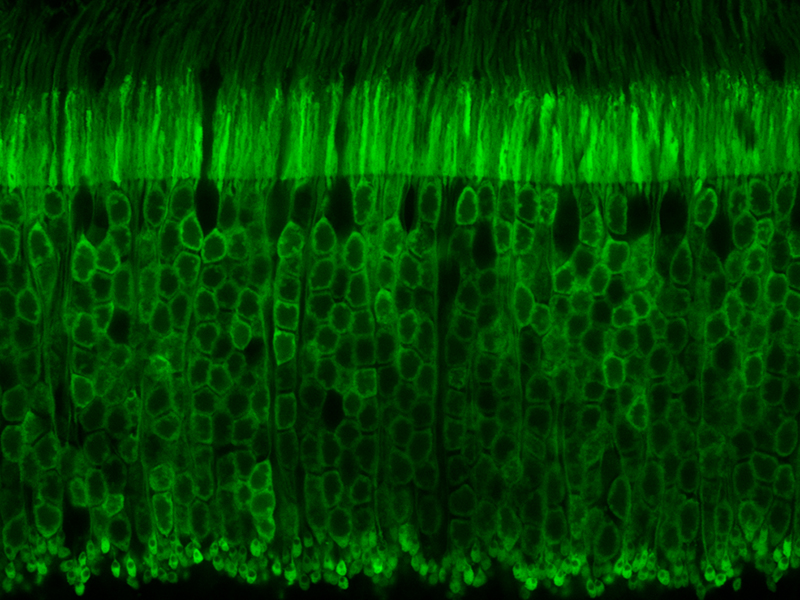

My research has centered on understanding the underlying cellular mechanisms and identifying novel treatments for neurodegenerative, neuromuscular, and inflammatory diseases. Most recently, I have been developing gene therapies for diseases that affect the eye like retinitis pigmentosa, uveitis, and age-related macular degeneration.

Earlier in my career I studied muscular dystrophies associated with mutations in dysferlin and members of the dystrophin-glycoprotein complex. While these are very different diseases from those that affect the eye, the underlying cell biology share common features. For example, inherited mutations can have a negative consequence on calcium signaling, cell membrane biology, or cytoskeletal dynamics, which ultimately cause different diseases depending on the cell type affected (i.e. muscle myofibers or retinal neurons).